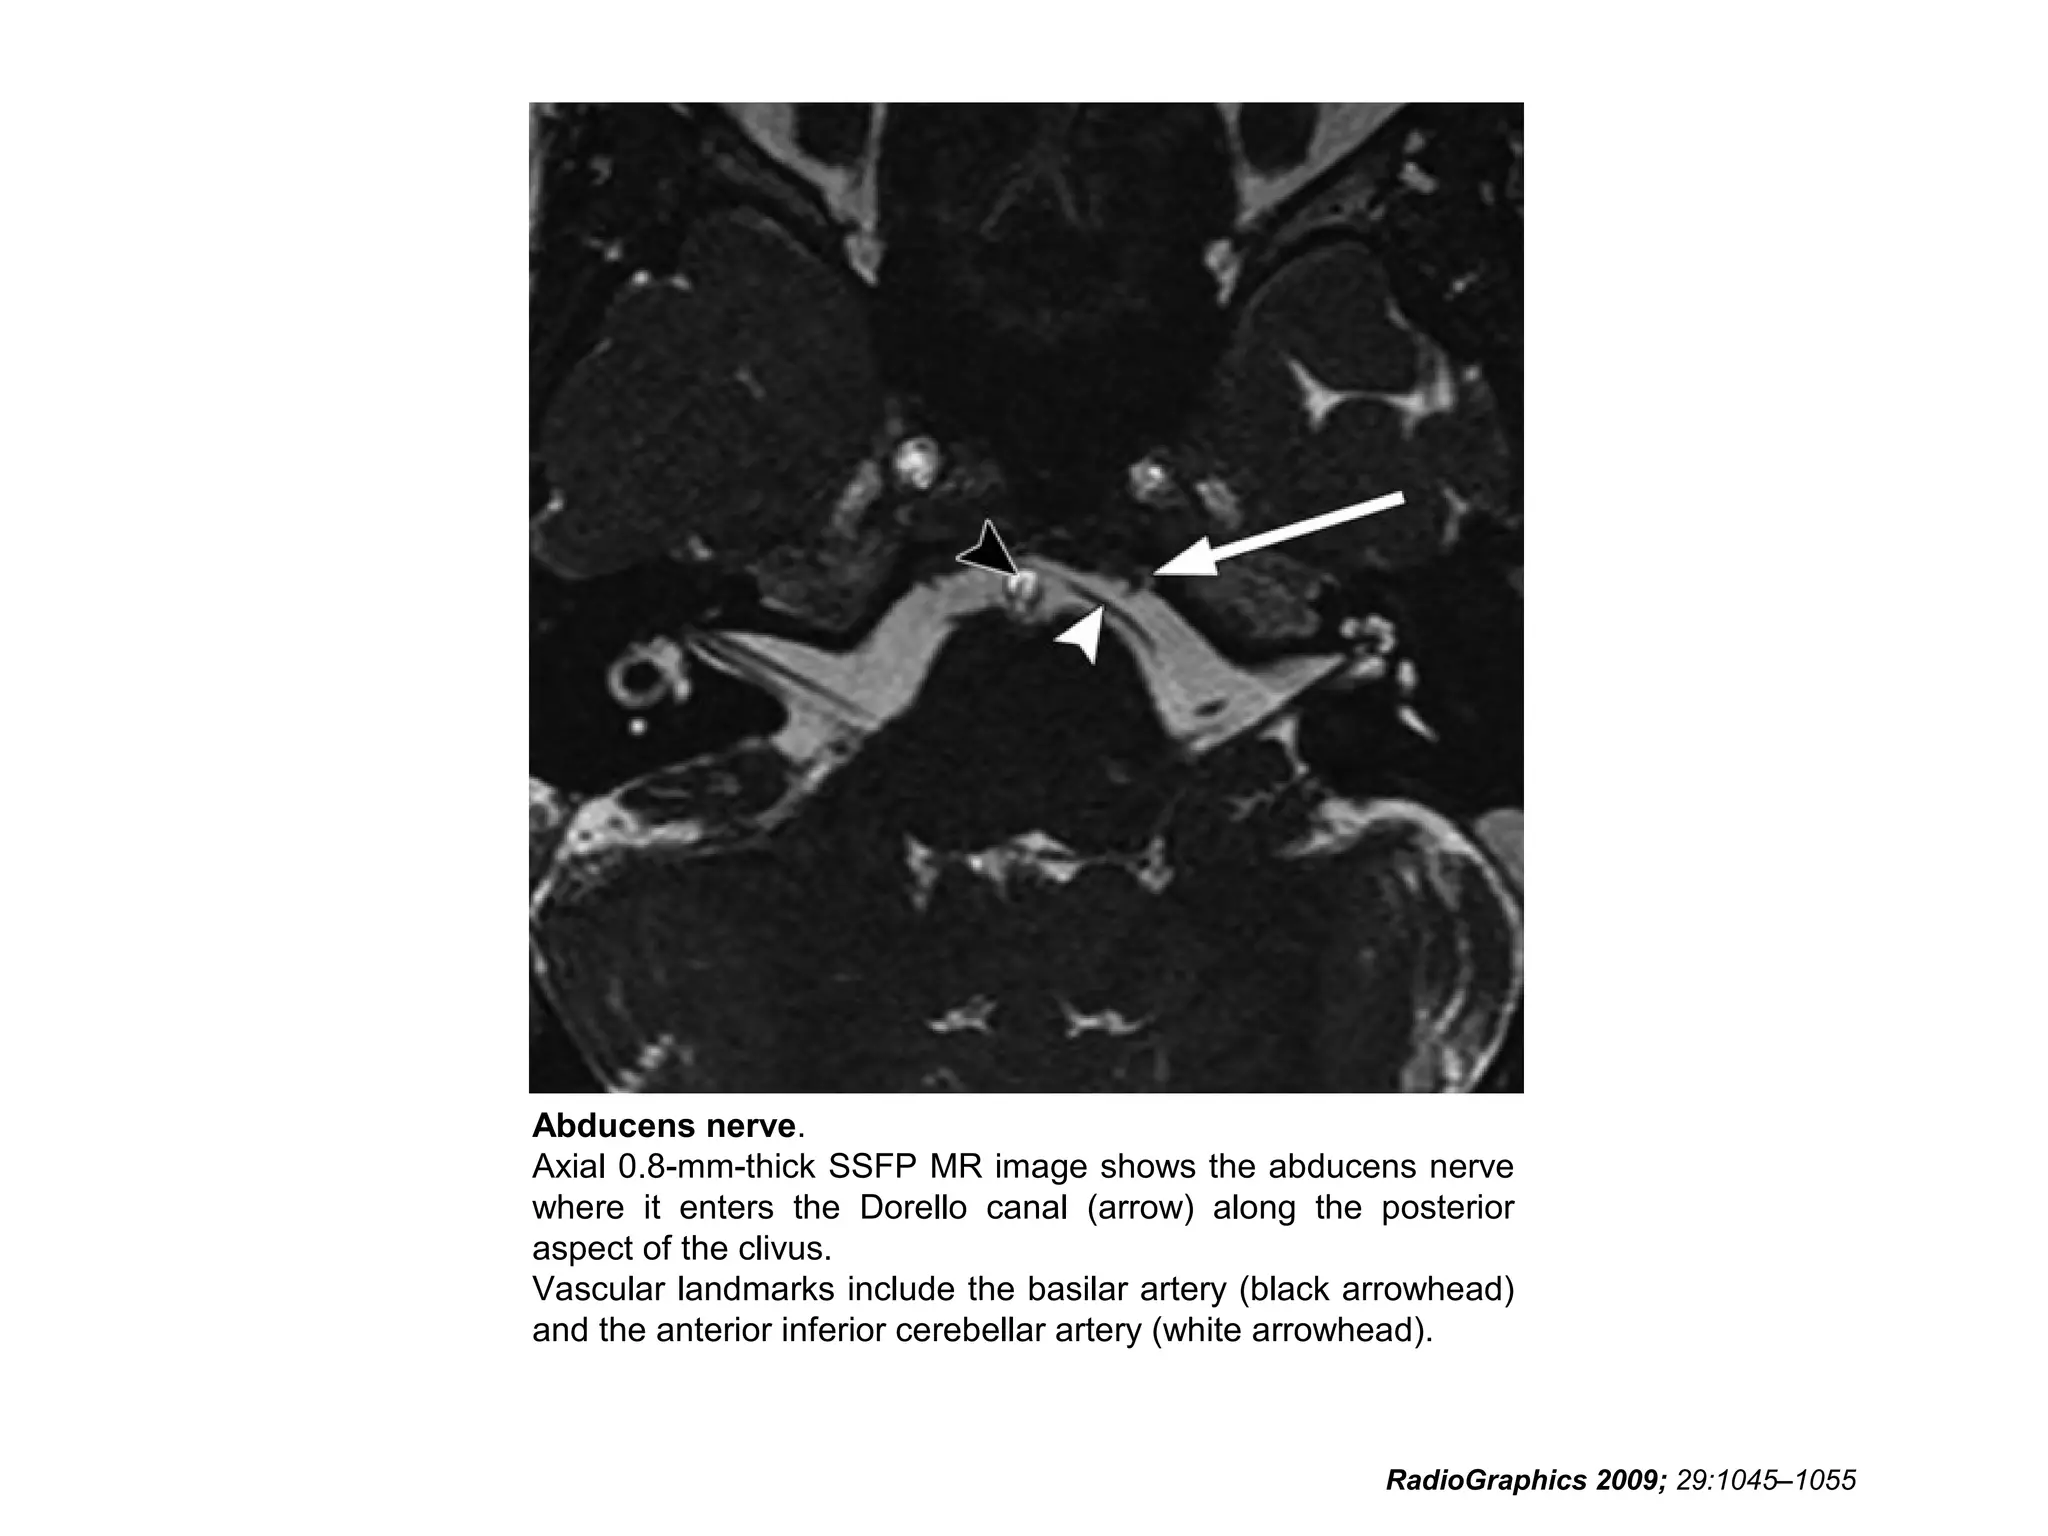

Cranial Nerve VI:

The Abducens Nerve

• The abducens nerve emerges from nuclei anterior to the

fourth ventricle, then courses anteriorly through the pons

to the pontomedullary junction and into the prepontine

cistern.

• After crossing the prepontine cistern in a posterior-to-

anterior direction, the abducens nerve runs vertically

along the posterior aspect of the clivus, within a fibrous

sheath called the Dorello canal.

• The nerve then continues over the medial petrous apex

and through the medial cavernous sinus, entering the

orbit through the superior orbital fissure to innervate the

lateral rectus muscle.

RadioGraphics 2009; 29:1045–1055

• It is important to note that the abducens nerve

runs almost the entire length of the clivus.

• Radiologists should be vigilant for clivus and

petrous apex abnormalities in the setting of

abducens nerve palsy.

• Although the abducens nerve lies near the

anterior inferior cerebellar artery and has a

similar caliber, the two structures course in

orthogonal directions and are thus easily

distinguished.

Abducens nerve.

Axial 0.8-mm-thick SSFP MR image shows the abducens nerve

where it enters the Dorello canal (arrow) along the posterior

aspect of the clivus.

Vascular landmarks include the basilar artery (black arrowhead)

and the anterior inferior cerebellar artery (white arrowhead).